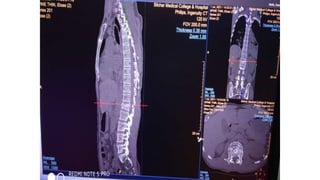

Burst fracture of L1 vertebrae

Saggital, Coronal and Axial

• 52.

Burst fracture ofL1 vertebrae Saggital, Coronal and Axial